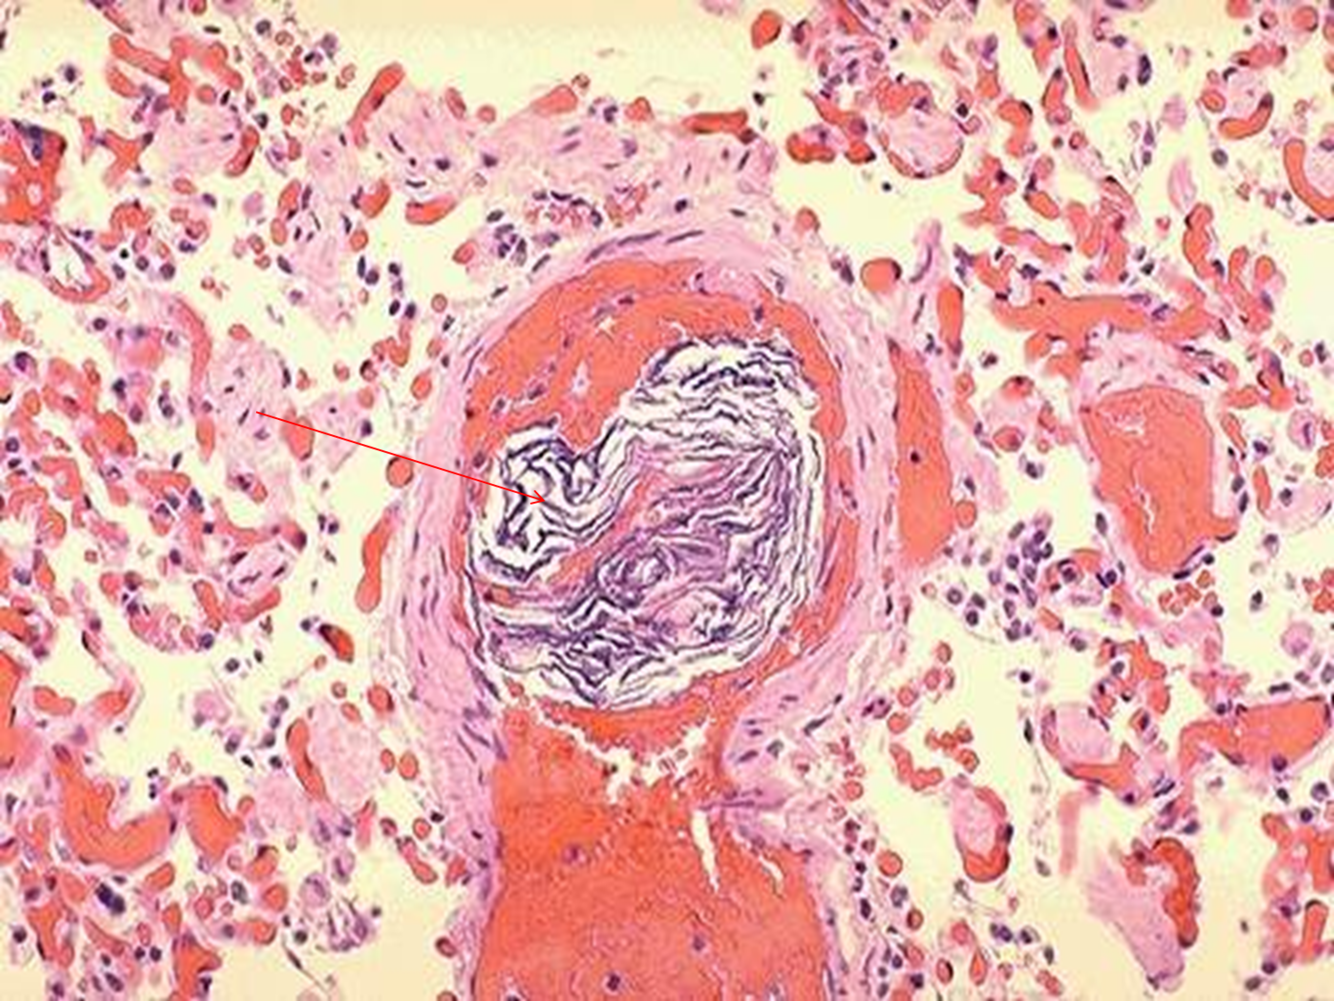

Dx?

Amniotic fluid embolism

(Swirly blue stuff = squamoid cells from fetal skin and amnion)